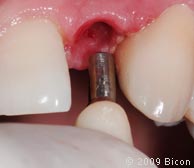

40. Очистка колодца имплантата ватным аппликатором и установка интегрированной коронки.

41. Очистка колодца имплантата ватным аппликатором и установка интегрированной коронки.